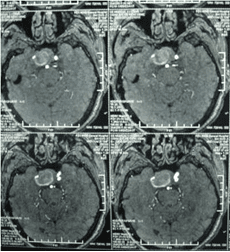

頸內動脈虹吸段巨大動脈瘤(約3cm ×3cm)

顱內動脈瘤是指腦動脈的局部性異常擴大,多在腦底動脈的分叉處或分支的夾角向外突出,多呈囊狀。TCD對顱內動脈瘤的總檢出率為67 %,動脈瘤>1cm的檢出率為82 %。TC D 對較大動脈瘤的檢測有其特征性表現,其典型表現為:瘤體內血流速度明顯低于載瘤動脈血流速度,其收縮峰陡峭或多峰不整,舒張期末流速極低或斷流,PI 值增高,多為雙向血流,聲頻低鈍,似撞擊樣轟鳴音。